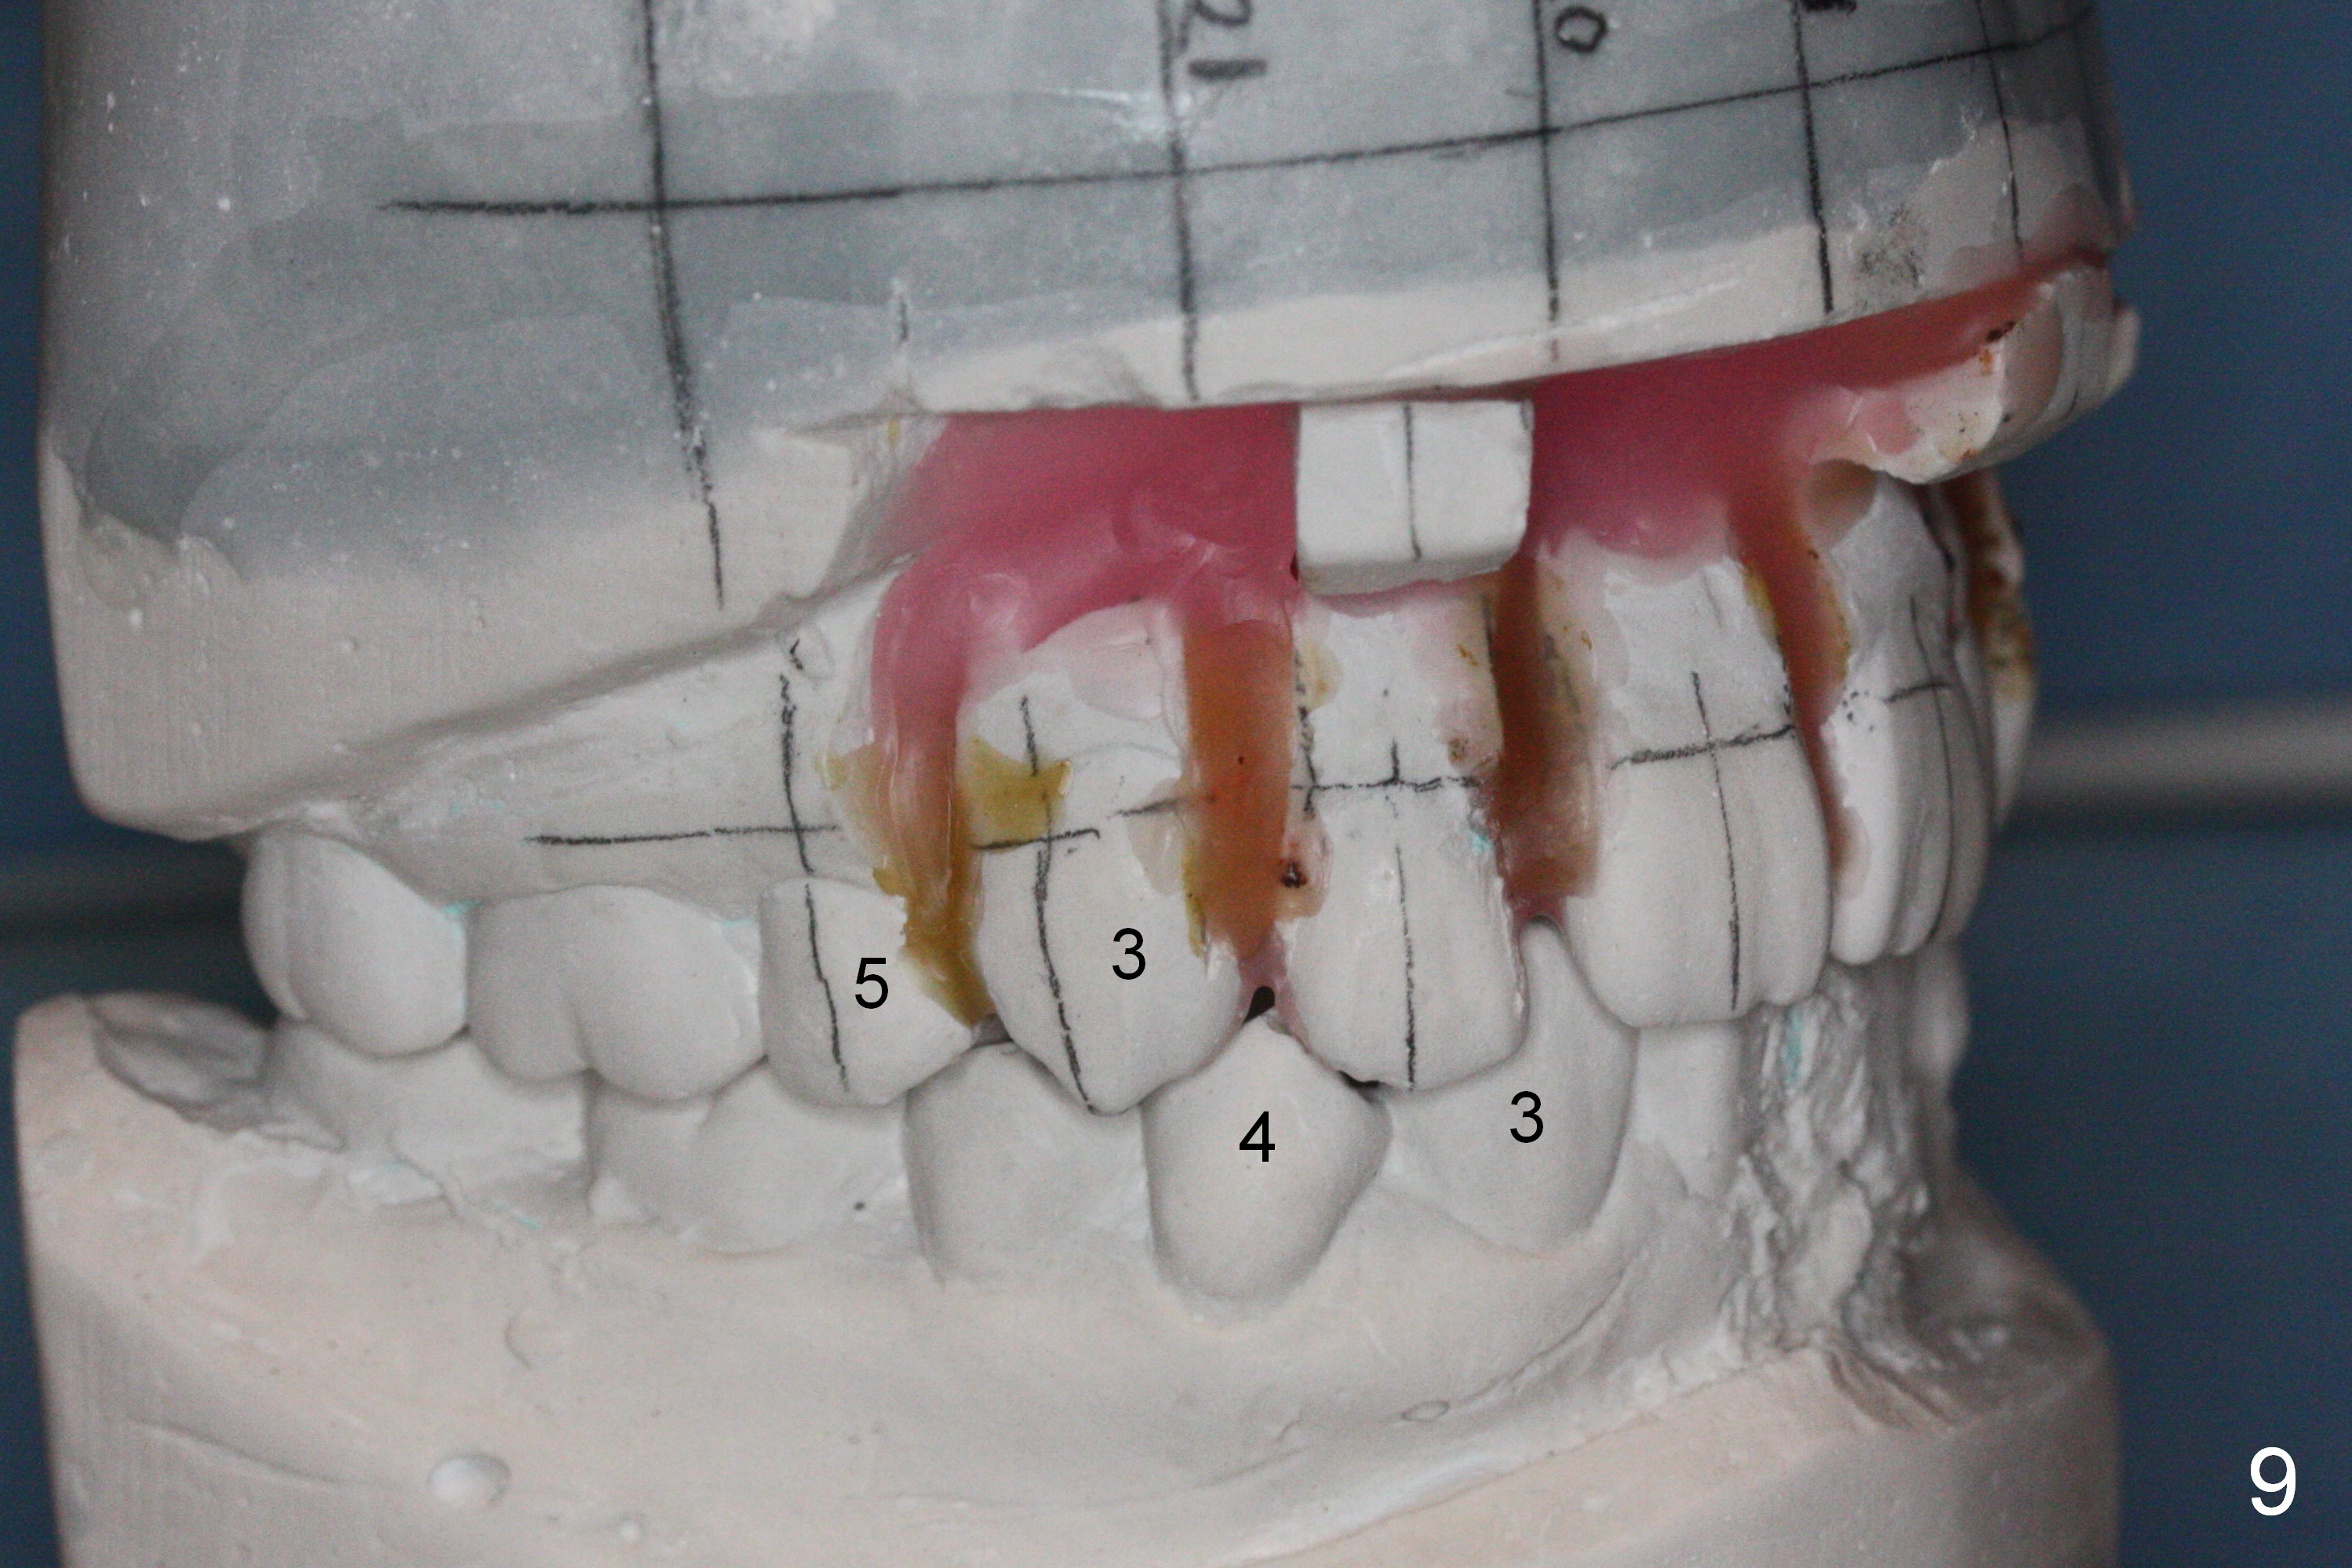

Wax up shows that there are diastemata between the upper teeth after U4s' extraction (Fig.9-11). It appears that L3s should be reduced as the incisors and that the upper posterior teeth should be mesialized. In that case, the mini-implants may be not needed.

The rotation of the upper canines is not corrected much in the next 3.5 months (Fig.21, as compared to Fig.18). Distalization of the upper right canine is implemented by power chain, but this is not sufficient because of the anterior deep bite. Note the tension of 18 niti wire between LR 3 and 4 (^). Mini implants are going to be placed mesial or distal to L3s (Fig.22,23 circles) to intrude the lower anterior teeth with elastic or power chain (Fig.23 red line, 24 black area). The upper anteriors will have space to be distalized (Fig.24 arrow). If necessary, proximal reduction will be accomplished at LR3 (extra wide, Fig.25 black outline) for further overjet correction (arrows).